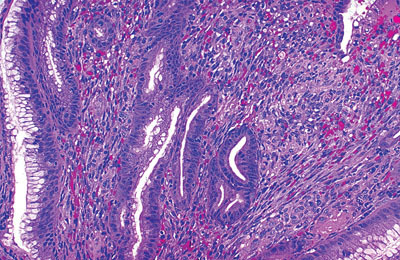

Kaposi sarcoma involving stomach

Four forms of Kaposi sarcoma (KS) are described:

(1) classic form, an indolent, primarily cutaneous disease typically affecting older men of Mediterranean ancestry

(2) endemic form, primarily affecting HIV-negative children in Africa

(3) iatrogenic form, affecting organ transplantation patients on immunosuppressive therapy

(4) HIV-associated cases.